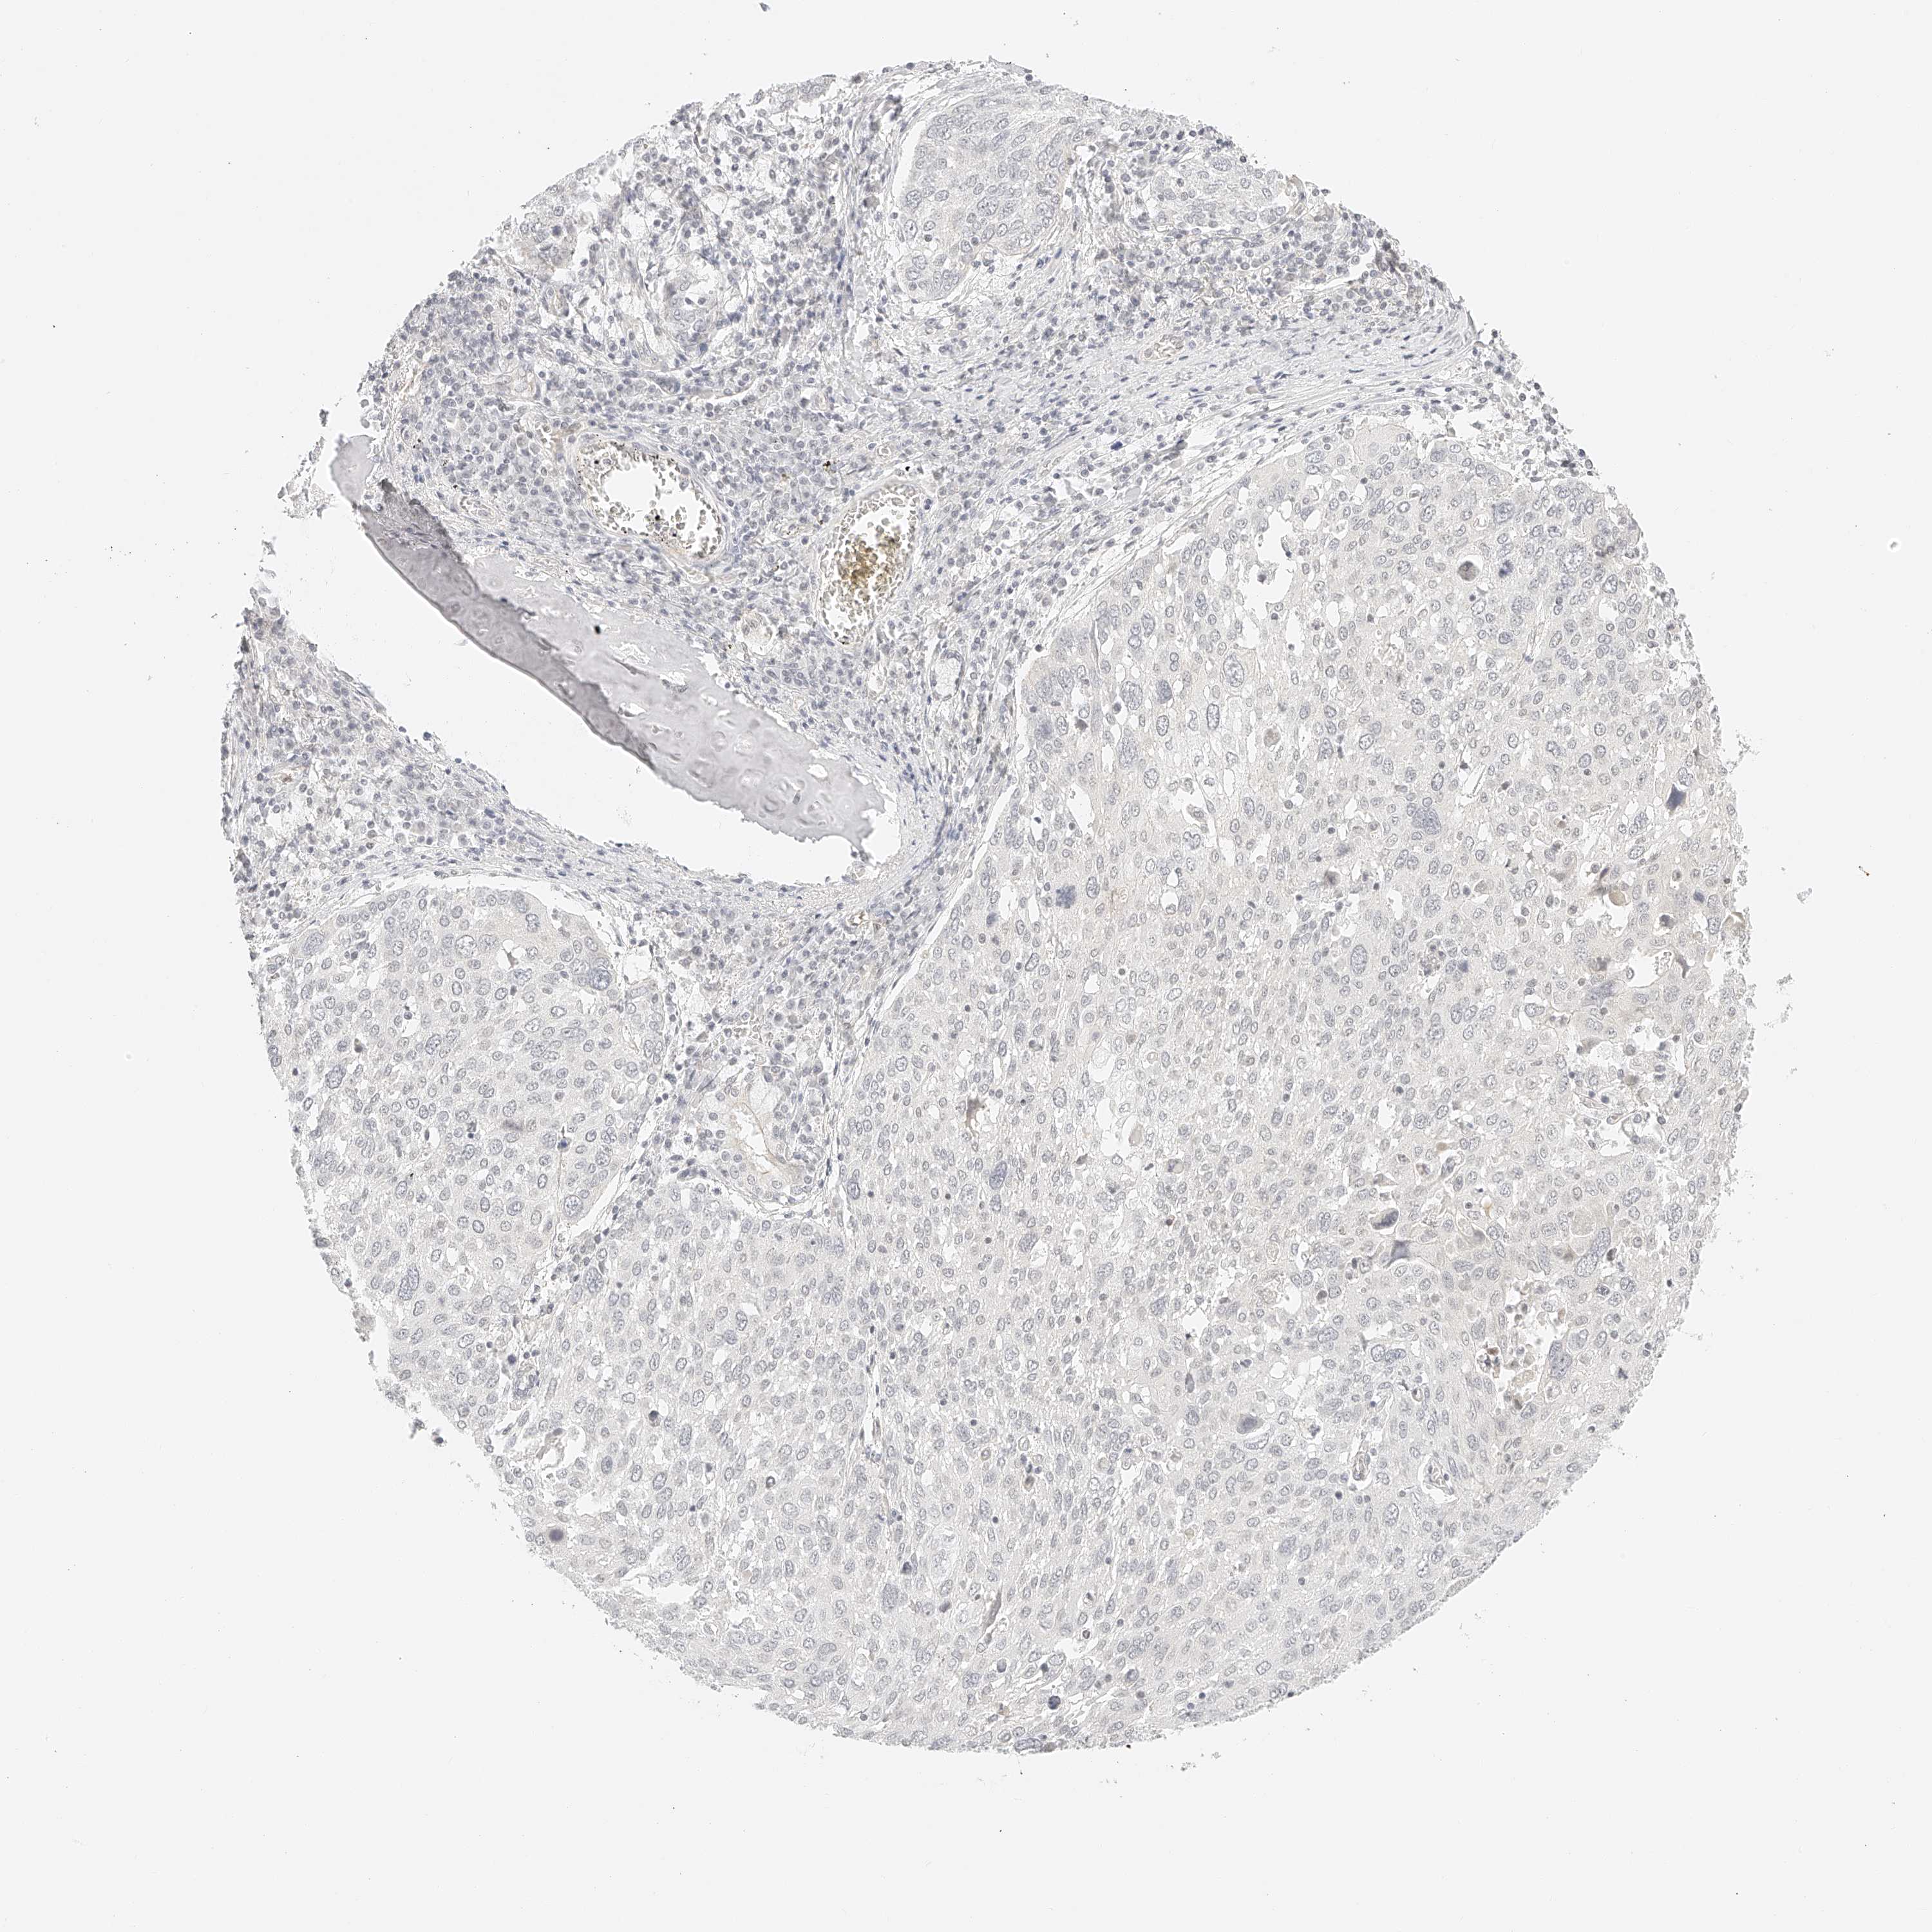

LUNG ADENOCARCINOMA (TCGA) - Interactive survival scatter ploti

The Survival Scatter plot shows the clinical status (i.e. dead or alive) for all individuals in the patient cohort, based on the same data that underlies the corresponding Kaplan-Meier plots. Patients that are alive at last time for follow-up are shown in blue and patients who have died during the study are shown in red.

The x-axis shows the expression levels (FPKM) of the investigated gene in the tumor tissue at the time of diagnosis. The y-axis shows the follow-up time after diagnosis (years). Both axes are complimented with kernel density curves demonstrating the data density over the axes. The top density plot shows the expression levels (FPKM) distribution among dead (red) and alive patients (blue). The right density plot shows the data density of the survived years of dead patients with high and low expression levels respectively, stratified using the cutoff indicated by the vertical dashed line through the Survival Scatter plot. This cutoff is automatically defined based on the FPKM cutoff that minimizes the p-score. The cutoff can be changed by dragging the vertical line or by entering a cutoff value in the square labeled "Current cut-off".

Under the Survival Scatter plot the p-score landscape (black curve; left axis) is shown together with dead median separation (red curve; right axis). Dead median separation is the difference in median mRNA expression between patients who have died with high and low expression, respectively. It is calculated as follows: median FPKM expression of dead patients with high expression - median FPKM expression of dead patients with low expression. This is intended to aid the user in visually exploring custom cutoffs and the associated p-scores and dead median separation.

Individual patient data is displayed and can be filtered by clicking on one or more of the category buttons on the top of the page. Categories describing expression level and patient information include: high, low, alive, dead, female, male and tumor stages. The scale of the x-axis can be toggled between linear and log-scale by clicking on the "x log" button. Mouse-over function shows TCGA ID, patient information and mRNA expression (FPKM) for each patient.

& Survival analysisi

Kaplan-Meier plots summarize results from analysis of correlation between mRNA expression level and patient survival. Patients were divided based on level of expression into one of the two groups "low" (under cut off) or "high" (over cut off). X-axis shows time for survival (years) and y-axis shows the probability of survival, where 1.0 corresponds to 100 percent.

ZFP69 is not prognostic in Lung Adenocarcinoma (TCGA)

: 3.7

Average pTPM 3.1

Number of samples 497